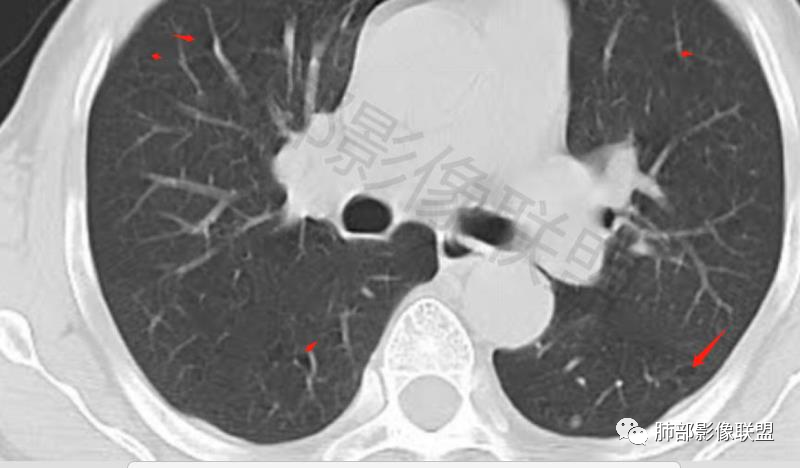

左肺下叶胸膜下结节,晕中毛刺,可见血管进入增粗,病灶中度均匀延迟强化,其他肺叶可见卫星病灶,考虑隐球菌。

男,60体检发现左肺下叶结节,左肺下叶类圆形结节影,边界清晰,边缘见浅分叶及细短毛刺,病灶内见增粗血管影穿行,相应层面胸膜增厚,双肺另见微小结节影,增强扫描病灶轻度强化,考虑隐球菌,除外腺癌。

老年男性,左肺下叶背段胸膜下孤立结节,整体圆顿,周围有晕,晕中毛刺,似乎支持隐球,但边缘有一囊腔,恶性不能除外!等答案!

左肺下叶胸膜下类圆形结节,无分叶,无胸膜牵拉,周围有晕,血管支气管进入,考虑隐球菌

左肺下叶胸膜下实性小结节,边缘可见毛刺,轻度收缩,近端与血管束相连,远端轻度牵拉胸膜,并远端可见小空泡,平扫密度均匀,增强后渐近性强化,考虑腺癌,鉴别隐球菌

老年男性,CT左肺下叶胸膜下类圆形结节,边缘光滑,无分叶,可见毛刺,相邻胸膜多条牵拉,局部胸膜增厚,(多见炎性病变),病灶周围可见模糊晕征,血管支气管进入,考虑隐球菌,现实中万万不能排除肺癌。

中老年男性患者,无症状体检发现,胸部CT:左下肺内前基底段近胸膜下类圆形结节,边缘清晰,周围晕征,周围毛刺细软,有胸膜牵拉及血管进入,增强扫描明显不均匀强化,考虑炎性肉芽肿,隐球菌可能,鉴别腺癌

图做的真漂亮!老年男性,双肺多发结节,最大者位于左肺下叶胸膜下,周围有晕,晕中毛刺,边缘有一囊腔,胸膜牵拉,持续强化,考虑隐球,鉴别腺癌。

左肺下叶胸膜下类圆形结节,边缘光滑,周围有晕,晕中有毛刺,周围可见小卫星灶,相邻胸膜增厚,血管进入,右肺中叶可见小结节影,考虑炎性肉芽肿,隐球菌。鉴别腺癌。

晨读:左肺下叶胸膜下实性小结节,边缘可见模糊晕及毛刺,轻度收缩,与支气管关系不清,近端与血管束相连,内见小空泡,平扫密度均匀,均匀强化。远近可见多个小结节。考虑炎性肉芽肿,隐球菌病,鉴别结核、腺癌。

老年男性,左肺下叶背段胸膜下结节,边缘毛刺,血管进入,斜裂有牵拉,局部胸膜糊墙,周围有晕,但有一囊腔,首先考虑腺癌,但是右肺中叶及左肺下叶还有其他结节,鉴别隐球菌

类圆形,边缘稍平直,周围晕中细微毛刺,密度均匀,均匀强化,血管走形自然,稍牵拉扭曲,支气管在近端堵塞